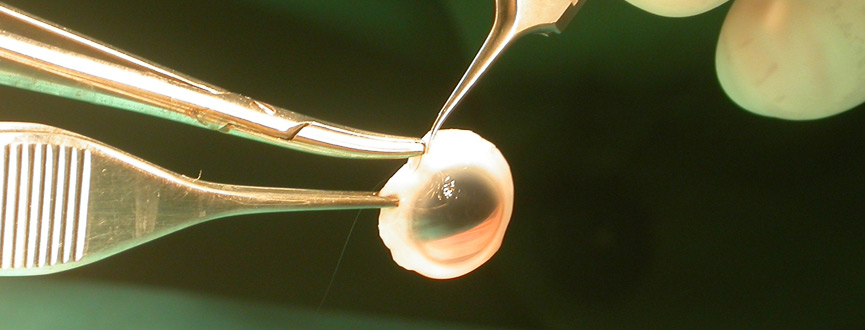

La cirugía es el único tratamiento eficaz y consiste en remover el cristalino opaco y reemplazarlo con un lente artificial.

La cirugía de catarata es el procedimiento quirúrgico que se realiza con mayor frecuencia a nivel mundial y actualmente la catarata se debe remover cuando la pérdida en la visión interfiere con sus actividades diarias, como manejar, leer o ver televisión. Usted y su oftalmólogo pueden tomar esta decisión juntos.

Durante la cirugía, la lente faquica se inserta a través de una incisión muy pequeña.

Una vez implantada, la lente se desdobla y se acomoda dentro del liquido que se encuentra entre el iris y el cristalino, el humor acuoso. En esa posición permaneces estable, indefinidamente, corrigiendo así la visión de la forma permanente. La incisión se cierra espontáneamente no siendo necesario dar punto halago de sutura.